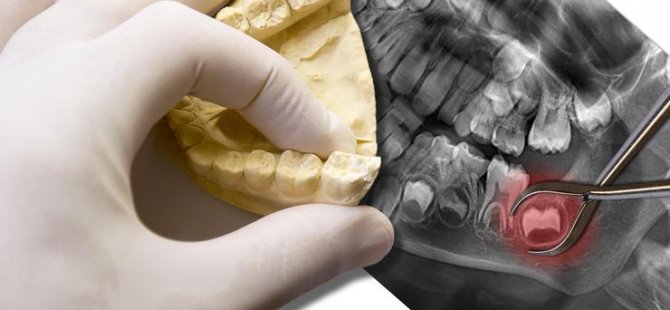

TAMAMEN GÖMÜLÜ 20'LİK DİŞLER ÇEKİLMELİ Mİ?

Gömülü 20 yaş dişleri, ağız boşluğuna tam olarak sürememiş üçüncü büyük azı dişleridir.

Gömülü 20 yaş dişleri, ağız boşluğuna tam olarak sürememiş üçüncü büyük azı dişleridir. Çoğu insanda üst çenede iki, alt çenede iki olmak üzere dört tane 20 yaş dişi bulunur fakat bazı insanlarda dört taneden az bulunabileceği gibi hiç oluşmayabilir.

Dişlerin dizili olduğu çene kemiğinde dişlerin ağız ortamına çıkmaları için yeterli yer bulunmaması, 20 yaş dişinin anormal bir konumda bulunması veya 20 yaş dişlerinin çevresinde bulunabilecek çenelere ait kist veya tümörlerin varlığı bu dişlerin kısmen veya tamamen gömülü kalmalarına sebep olabilir. 20 yaş dişleri kısmen veya tamamen gömülü kalabilir. Tamamen gömülü 20 yaş dişleri komşu dişlerde; çürük, diş eti iltihabı veya çevre dokularda kistik oluşumlara sebep olmadıkları sürece çekilmek durumunda değillerdir. Radyolojik ve klinik olarak takip edilmeleri yeterlidir.

Kısmen gömülü 20 yaş dişleri, ağız ortamına tamamen çıkamamış, üzerleri kısmen diş eti ile örtülü 20 yaş dişleridir. Üzerlerini kısmen örten diş eti nedeni ile gıda birikimine ve bakteri plağı oluşumuna uygun bir zemin hazırlayabilirler. Bu dişlerin, diş dizisinin en arka bölgesinde yer almaları hijyen gerekliliklerinin sağlanmasını da zorlaştırır. Tüm bu durumlar bir arada düşünüldüğünde bu dişler; çürüme veya üzerlerini örten diş etinde perikoronitis olarak adlandırılan ve genellikle tekrarlayan bir enfeksiyon tablosu olarak karşımıza çıkan bir klinik durum yaratma eğilimi gösterirler.

Bu enfeksiyon durumu; basit lokal bir enfeksiyon tablosu olarak kalabileceği gibi tedavi edilmezse ilerleyen dönemlerde hayati tehlike oluşturabilecek baş boyun apselerine neden olabilir. Bu sebeplerden ötürü çenelerimizde tamamen sürmeyi başaramamış 20 yaş dişlerinin gerekli klinik ve radyolojik muayene sonrasında uygun cerrahi yöntemler ile çekilmesi gerekir.